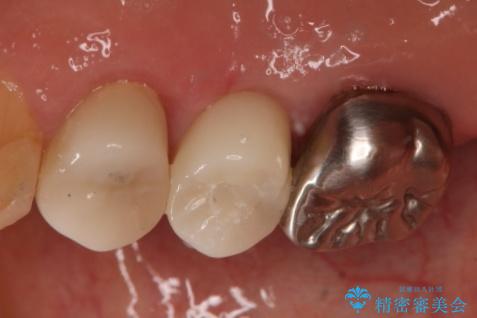

- 右上小臼歯の破折を理由に来院された患者様です。

残根状態で保存不可能と判断し、抜歯した上で補綴することを提案しました。

インプラント治療を希望されたので治療の期間・回数の少ない抜歯即時埋入インプラントでの治療を計画しました。